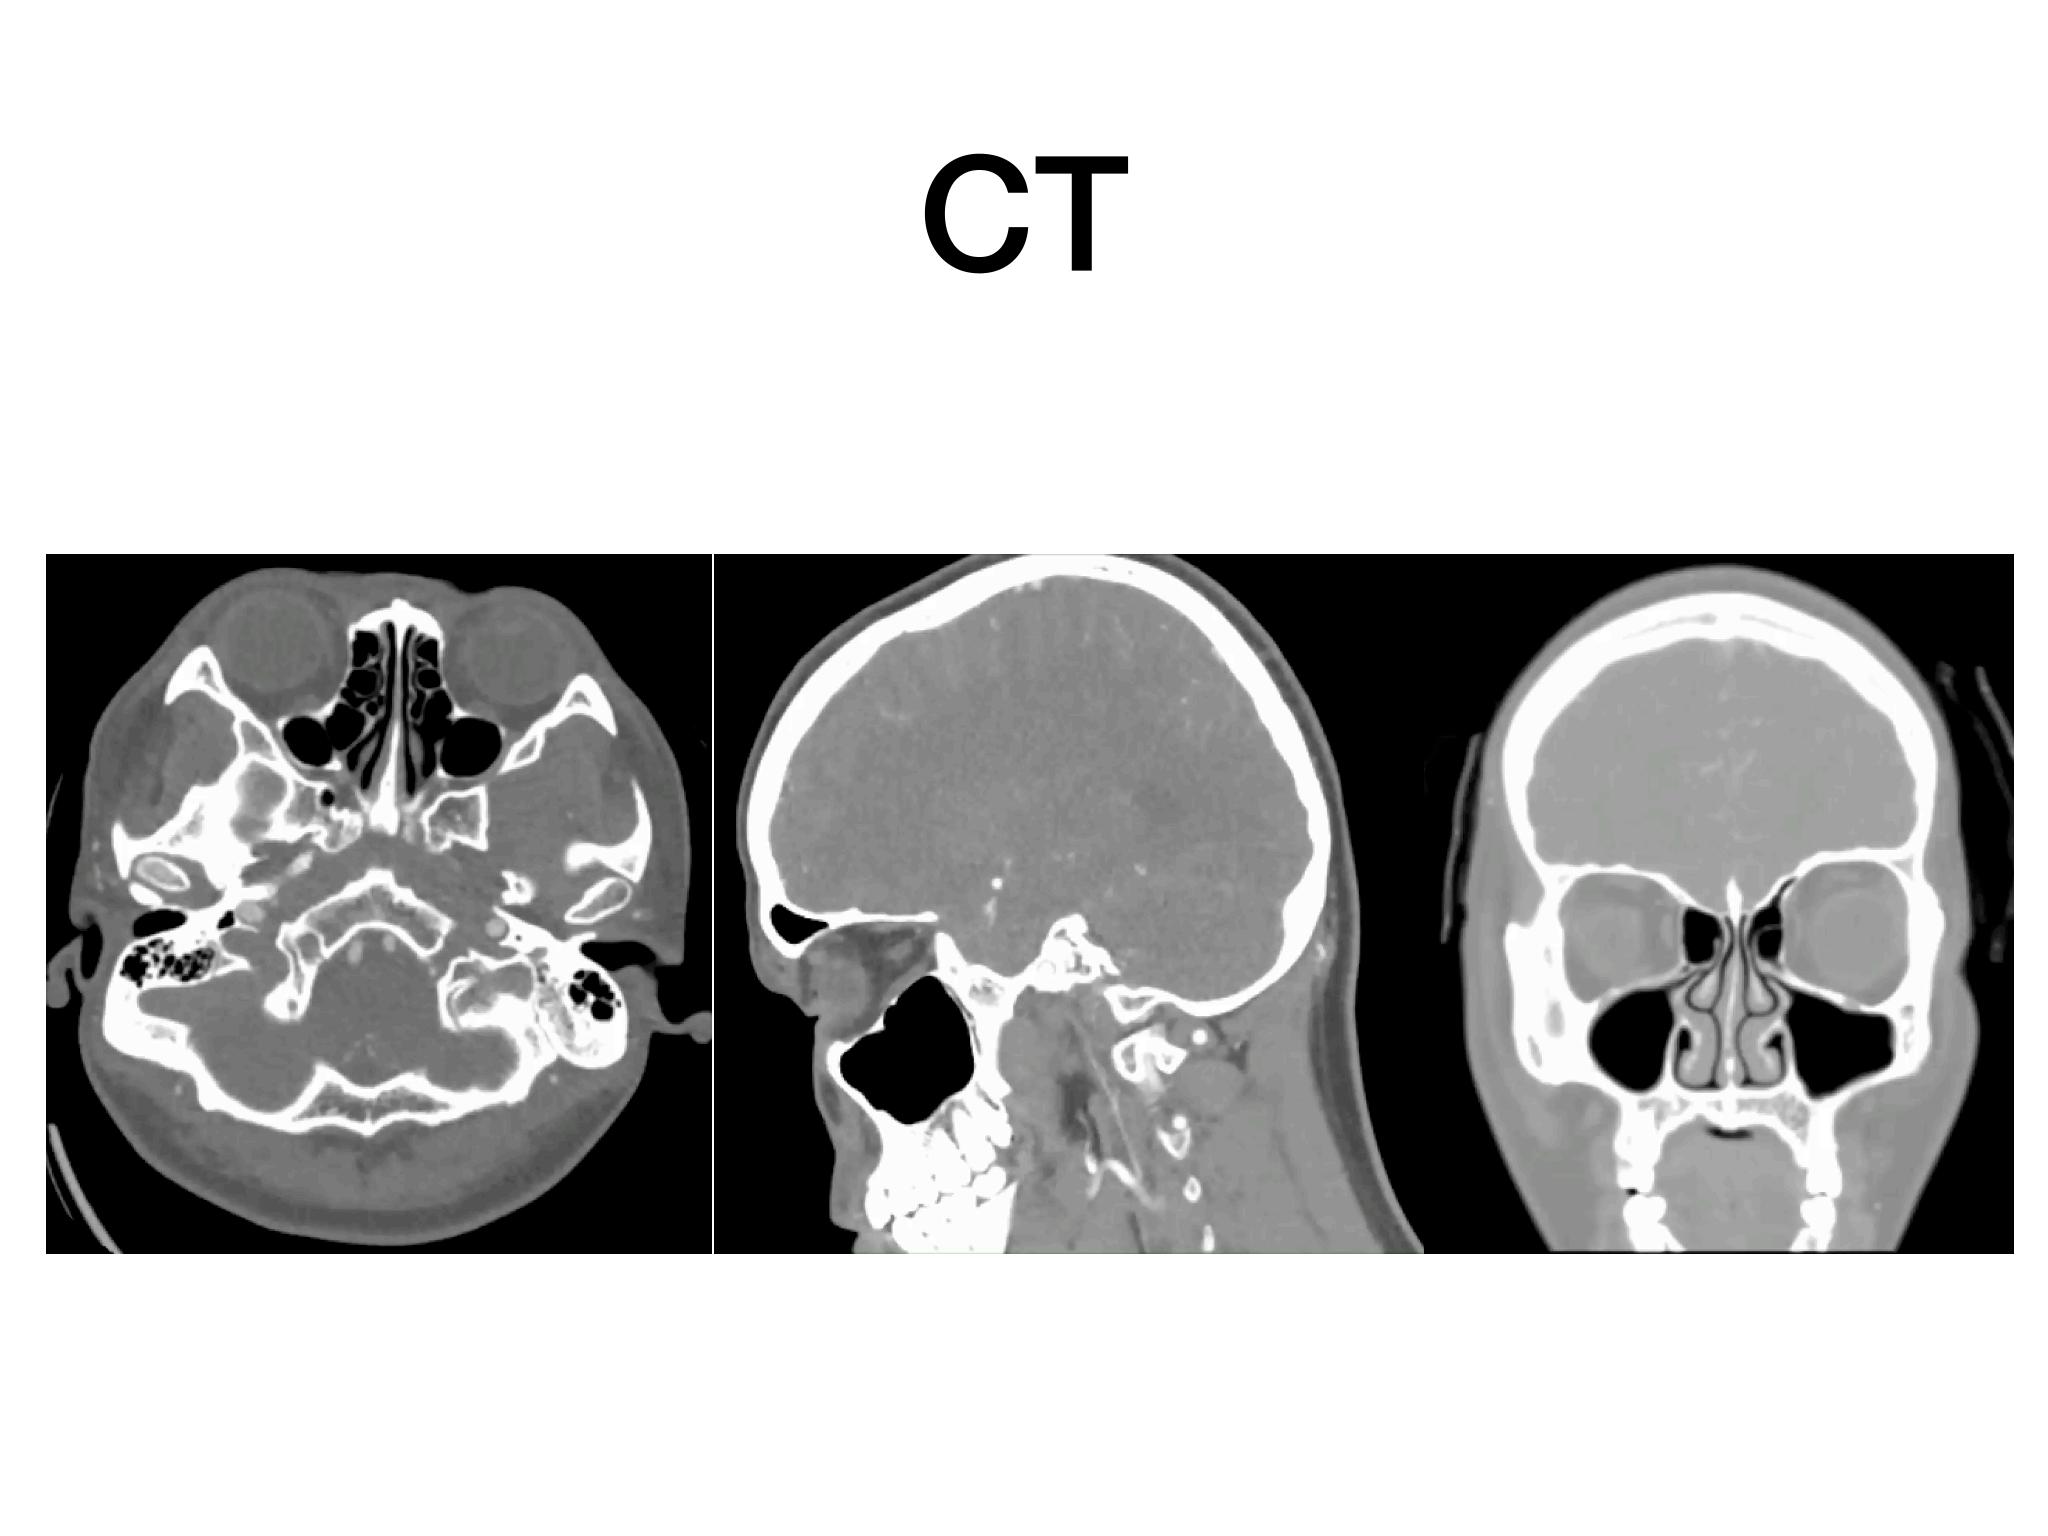

分享一例经鼻内镜泌乳素大腺瘤切除手术,患者青年男性,术前泌乳素>200ng/dl,MR提示大腺瘤合并瘤内出血,手术全切肿瘤,术后泌乳素降至正常,生化缓解,预后良好。